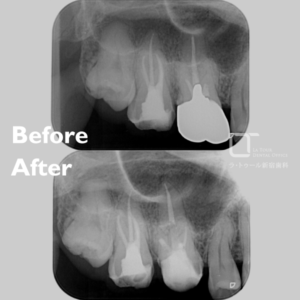

セラミック治療・40代(女性)|「歯科治療への恐怖心が強い方に静脈内鎮静下で3本同時修復」

治療内容 セラミック治療(アンレー) 施術費用 88000円×3本(別途鎮静代) 通院回数 2回 通院期間 メリット 審美性に優れており、天然歯に近い自然な色や形に仕上がります。金属を使わないため、金属アレルギーの心配がなく、高い適合精度と耐久性によって、美しさと機能を長く維持しやすくなります。 リスクと副作用 セラミック治療は保険適用外(自由診療)です。強い衝撃や過度な力が加わると、まれに割れることがあります。治療後にしみる症状がみられることがありますが、多くは時間とともに落ち着いていきます。 セラミック治療の治療例です。歯科治療に対する恐怖心が強く、 […]